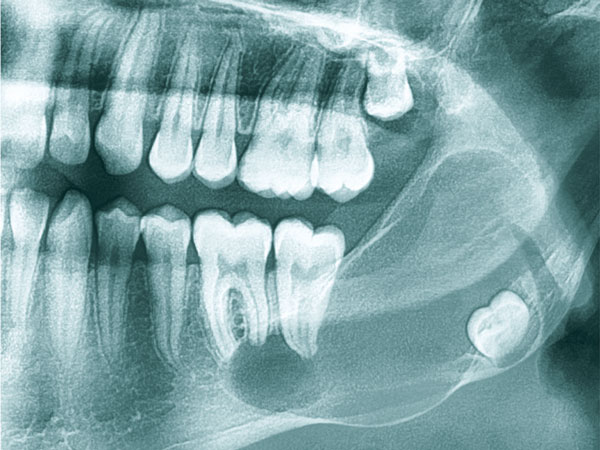

İnkşafı və böyüməsi tədricən baş verdiyindən, bu proses pasiyent tərəfindən demək olar ki hiss edilmir. Yalnız törəmənin ciddi ölçülərə çatması nəticəsində və ya iltihablanması nəticəsində meydana çıxan kliniki əlamətlər nəticəsində aşkarlanır. Əksər hallarda isə çəkilən diş və çənə rentgen şəkillərində təsadüfən rast gəlinir.